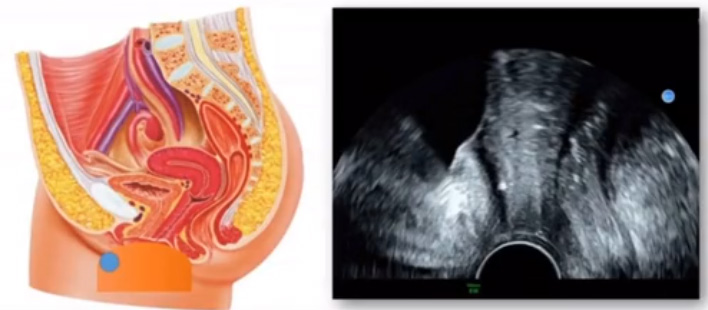

超聲DR探測(cè)途徑和探測(cè)方法,主要是有四個(gè)途徑,經(jīng)腹壁超聲探測(cè)檢查前準(zhǔn)備:適當(dāng)充盈膀胱探頭頻率:3.5-5.0MHz體位:仰臥位優(yōu)點(diǎn)是:適用范圍廣,切面及角度靈活,利于盆腔內(nèi)臟器及鄰近臟器全貌的顯示,經(jīng)陰道超聲探測(cè)檢查前準(zhǔn)備:排空膀胱探頭頻率:5-7.5MHz體位:膀胱截石位,優(yōu)點(diǎn):不受腹壁厚度、膀胱充盈程度、腸氣干擾的影響,良好顯示器官內(nèi)部。細(xì)微結(jié)構(gòu),經(jīng)陰道超聲檢查適應(yīng)癥,有性生活史的婦女監(jiān)測(cè)卵泡發(fā)育及子宮內(nèi)膜改變,預(yù)測(cè)排卵時(shí)間,發(fā)現(xiàn)卵泡發(fā)育異常,盆腔較小腫物的探查,早早孕檢查,急腹癥患者,膀胱無法充盈者。陰道超聲檢查的禁忌癥禁忌癥:未婚婦女(無性生活史),陰道畸形,月經(jīng)期,妊娠期,相對(duì)禁忌癥:先兆流產(chǎn)各種病因?qū)е玛幍莱鲅?,如需檢查須嚴(yán)格消毒后,如檢之物超出盆腔者,如宮內(nèi)孕達(dá)15周以上、較大子宮肌瘤和卵巢腫瘤,急性盆腔感染。經(jīng)直腸超聲探測(cè)·檢查前準(zhǔn)備、體位及檢查方法以及超聲圖像均同經(jīng)陰道超聲,檢查前準(zhǔn)備:排空膀胱,探頭頻率:5-7.5MHz,體位:膀胱截石位,適用癥:未婚婦女(無性生活的婦女)已婚但陰道有畸形腔內(nèi)探頭不能進(jìn)入者,經(jīng)會(huì)陰超聲探測(cè)主要在盆底。檢查前準(zhǔn)備、體位及檢查方法同經(jīng)陰道超聲:檢查前準(zhǔn)備:排空膀胱,探頭頻率:凸陣、線陣、腔內(nèi)探頭均可。體位:膀胱截石位,適用癥,所有婦女。